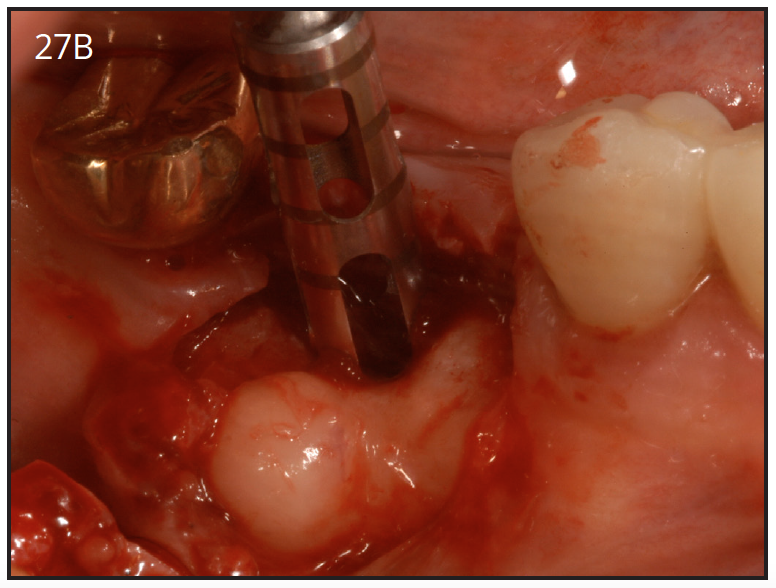

Mechanical complications include loosening of screws, fractured screws and even fractured implants due to force overload. However, the incidence of fixture fracture has been reported to be less of an issue than that of tooth fracture10 (Figure 27A, 27B).

Figure 27B – Gingiva incised and a trephine drill used to remove fractured implant

Figure 27B